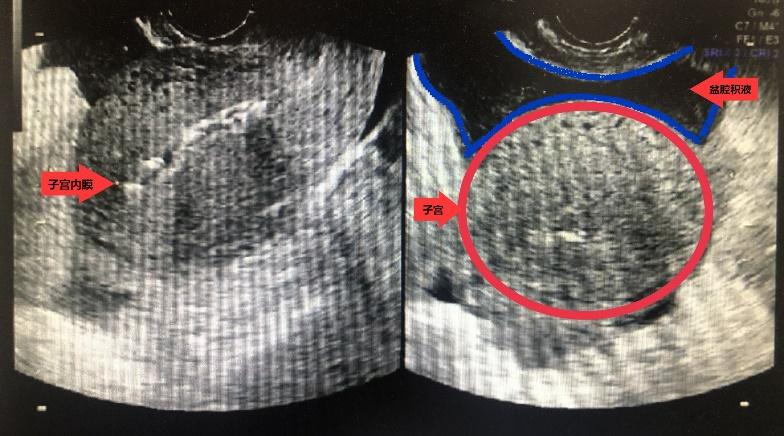

图二 病理性盆腔积液,特点:量多,透声欠佳

病理性盆腔积液——在临床上大部分女性的盆腔积液是由于炎症引起的,是盆腔存在炎性渗出物,病理性盆腔积液最常见的原因是盆腔炎、附件炎或者子宫内膜异位症引起的,少数有可能由结核、肿瘤或者宫外孕破裂、黄体破裂引起。这类女性大部分都有症状,比如下腹痛、下腹坠胀、腰骶部酸痛、月经失调、白带增多等。值得一提的是,除了妇科疾病,当患者出现肾衰、肝硬化、慢性心功能不全等心、肝、肾疾病时,也可能出现盆腔积液的情况。这时候就需要医生进行正确的判断,积极治疗患者的原发疾病。